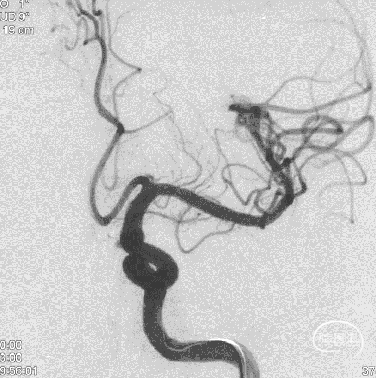

术后半年复查

6、Tubridge Plus材料改进后通体显影,可以更好观察支架的贴壁性及术中打开情况,提高释放安全性。

7、术后半年复查动脉瘤治愈,且未发生支架远近端狭窄及内膜过度增生,治疗效果满意。

8、同侧A1动脉瘤在FD保护下无变化。